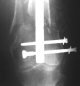

THX, initial images are

1,

2.

At that moment we had in stock only the 10 mm solid nails so of course there was no idea about early weight bearing. But it was quite enough for early knee ROM excersises (see attached). Two locking screws through the distal block provided that.

A new toy is more interesting and fashionable. And anyway it is not panacea, i have already seen presentations with LISS failures like the attached one presented by D.Seligson. And people also demonstrated incisions say that the method is not so LESS invasive as it supposed to be.